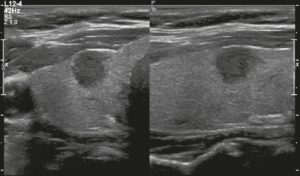

Hình 20. Hình ảnh nhân giáp hỗn hợp đặc và nang (1 điểm), đồng âm (1 điểm), rộng hơn cao (0 điểm), và lan rộng ra ngoài giới hạn phía trước của tuyến giáp (3 điểm), không có các ổ tăng âm hay bóng lưng (0 điểm). Do đó, tổng điểm là 5 điểm và mức độ nguy cơ được phân loại là TR4.